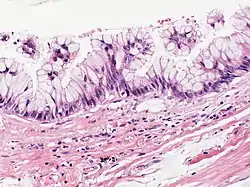

| Atypical goblet cells with focal tufting. The classification of these rare neoplasms is difficult and controversial. There appears to be a spectrum of mucinous cystic tumors ranging from those that are obviously benign (benign epithelium and no tumor invasion into surrounding lung) to those that exhibit invasion into surrounding lung tissue and are, therefore, malignant. In between is a group of neoplasms that exhibit epithelial atypia but no tumor invasion into lung tissue and the malignant potential of these is uncertain. This case appears to fall into that category. Focal cyst rupture with extravasation of mucin into surrounding lung tissue may occur with all types of mucinous cystic tumors. | |